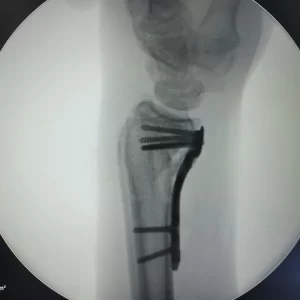

Placas para radio distal

RÁDIX Yuxta

Rádix Plus

Indicaciones

Fracturas en la porción distal del radio simples y complejas

con compromiso intra y extra articular.

Materiales

Titanio para implantes

Presentación Set

Derechas e Izquierdas 3 y 4 Orificios.

Para usar con:

» Tornillo Cortical Autotarrajante 2.7 mm – Titanio

» Tornillo de Bloqueo 2.4 mm – Titanio